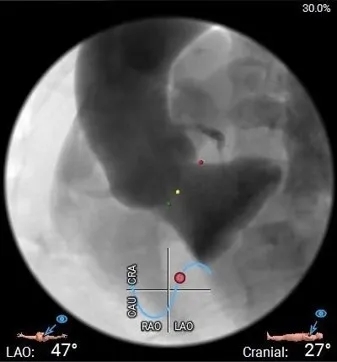

工作体位

右窦居中

左冠切线

左右重叠

主动脉根部造影